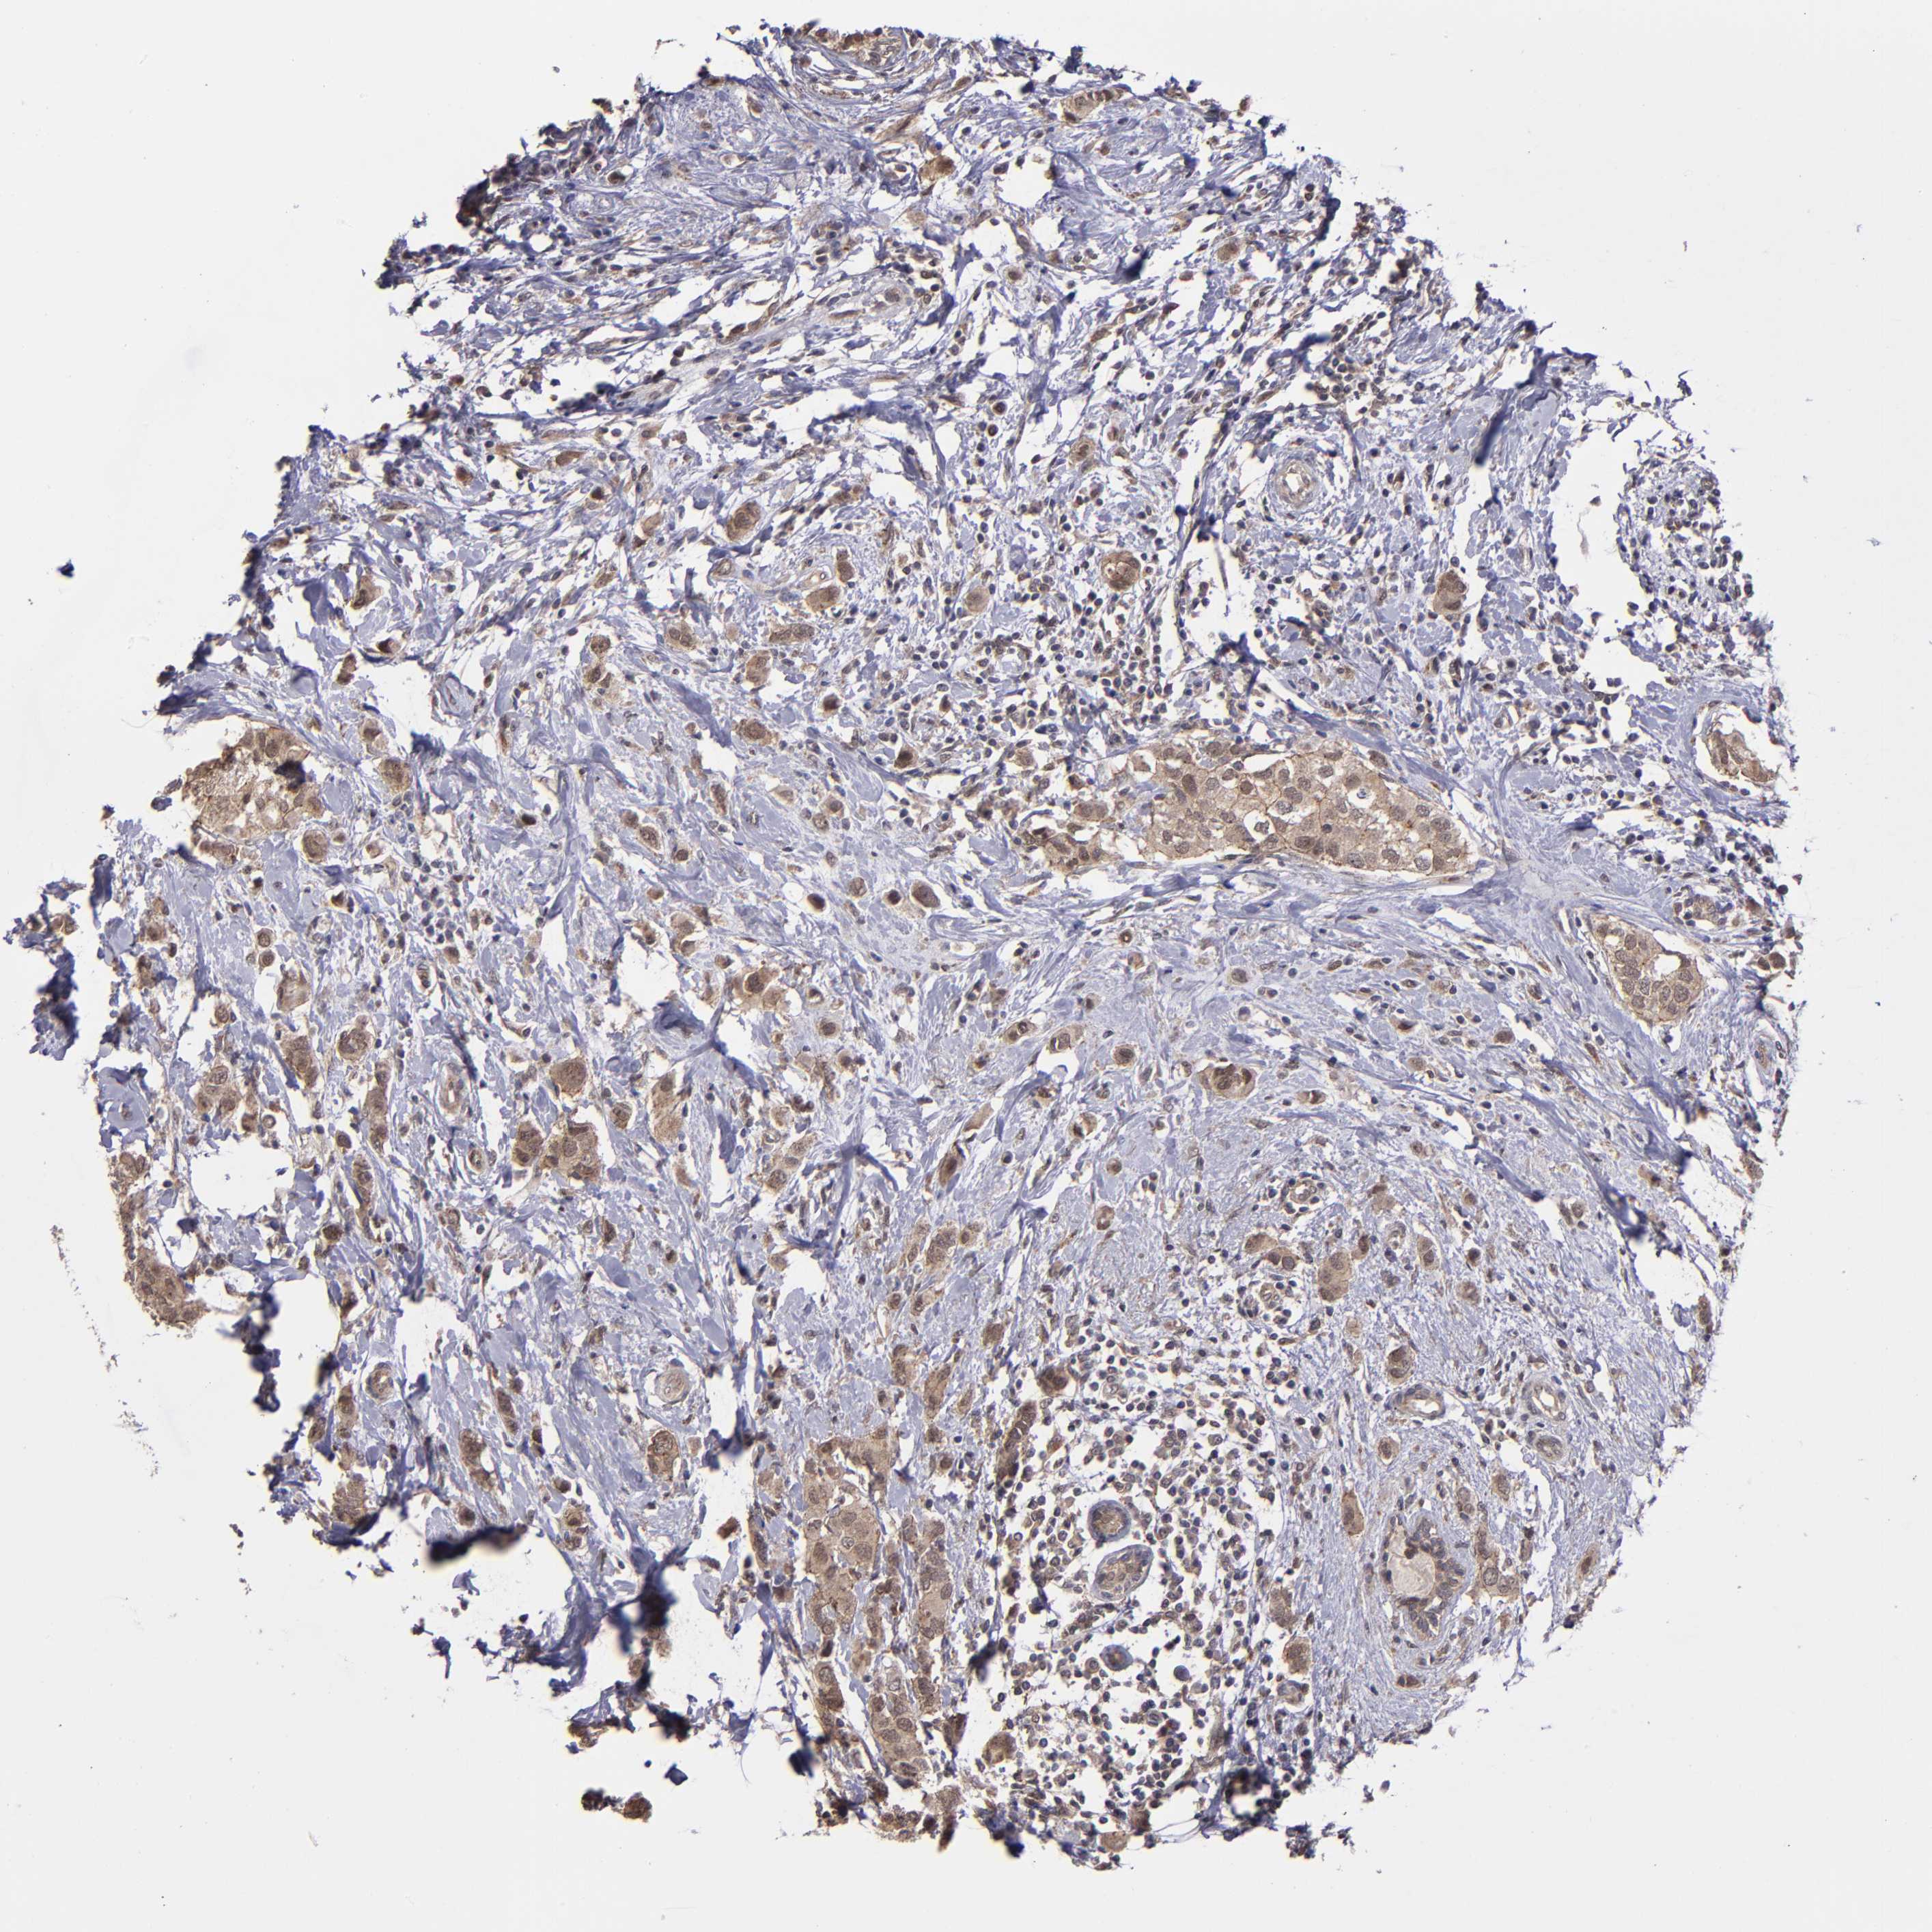

BRCA TCGA BRCA VALIDATION PROTEIN EXPRESSION